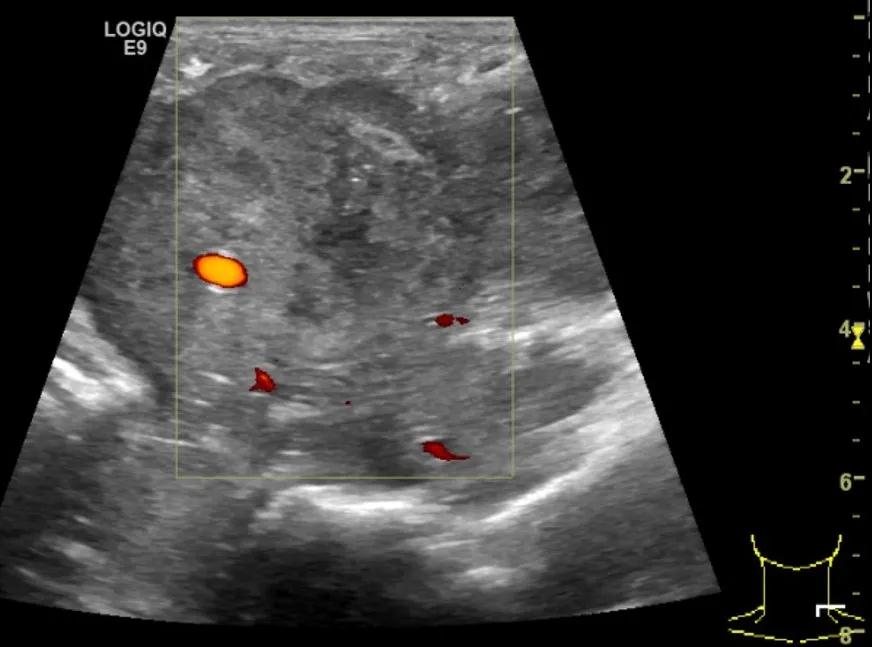

第四例是胸腺癌化妆包,术后、化疗之后淋巴结转移,肿块范围巨大,99mm*61mm,边界不清,呈浸润状,肿块包绕颈动脉,颈内静脉压闭,症状明显。由于患者放化疗也不敏感、血供非常丰富,于是采取多点姑息性消融。姑息性消融后未实现完全消融,病灶大片坏死,肿胀疼痛得到明显的缓解,后续患者未再来复查。

(病例4图例)